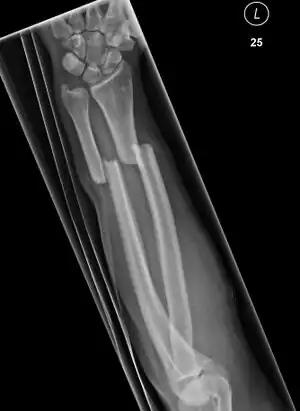

Front view of bowing fractured radius and ulna